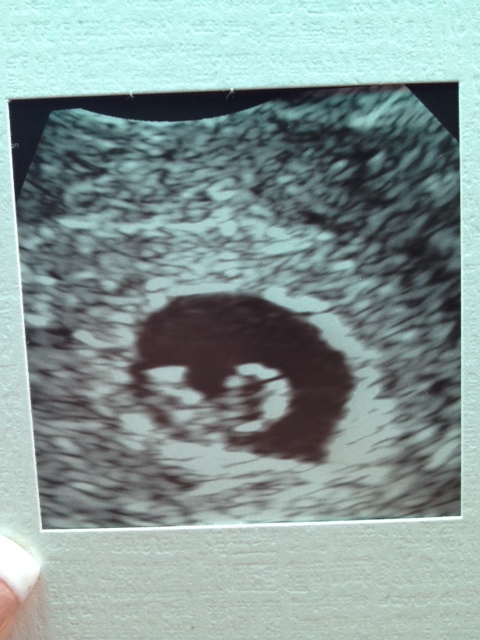

My time has finally come. I get to intro on the PAIF board. Holy hell has it been a tough few years but each month, day and minute has been worth it. 4 fresh IVF cycles and 1 FET later I'M FINALLY PREGNANT!!! ((happy crying))) I went for my first sonogram today and I am happy to report that we have one little baby "justone13" snuggled up! My DH and I are beyond thrilled. It finally feels real now after seeing it. We had a heart rate of 121 today and I go back in 2 weeks for my last scan ... and then I graduate! WOW!

I know most of you all over here from the IF board but look forward to meeting some new women on this incredible journey too. Here is a picture of our little snowflake.

First Scan January 5th! Everything looks great! Heart rate of 121!